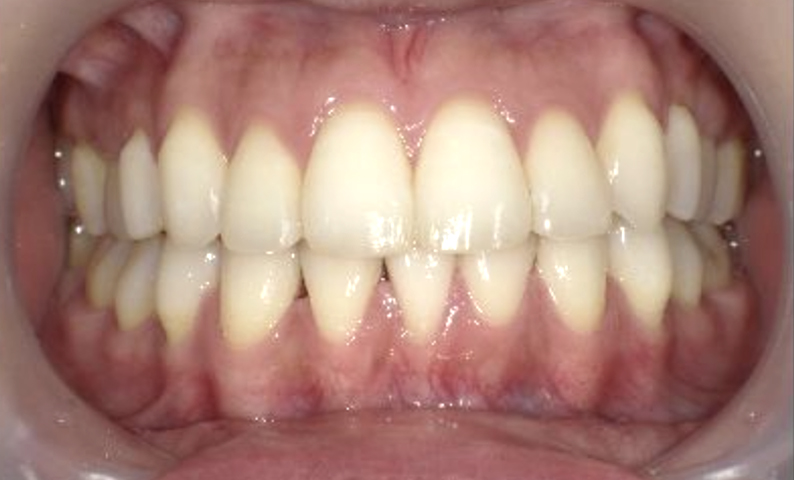

症例_001 上下顎の部分矯正

治療期間:10ヶ月金額:51万円+税女性八重歯前歯のガタガタ

| Before | After |

|---|---|

|